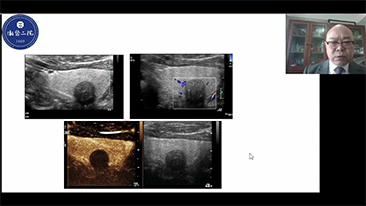

혈관종 또는 간암과 같은 국소적인 간 병변의 경우 초음파 대조 영상은 중요한 역할을 합니다. 초광대역 비선형 UWN+ 대조 영상 기술은 낮은 MI세팅과 길어진 조영제 확산 시간 관찰을 통해 보다 나은 침투력, 보다 높은 조영 조직비를 확보할 수 있습니다.

How clear can you see a liver

간을 얼마나 선명하게 관찰할 수 있을까요?